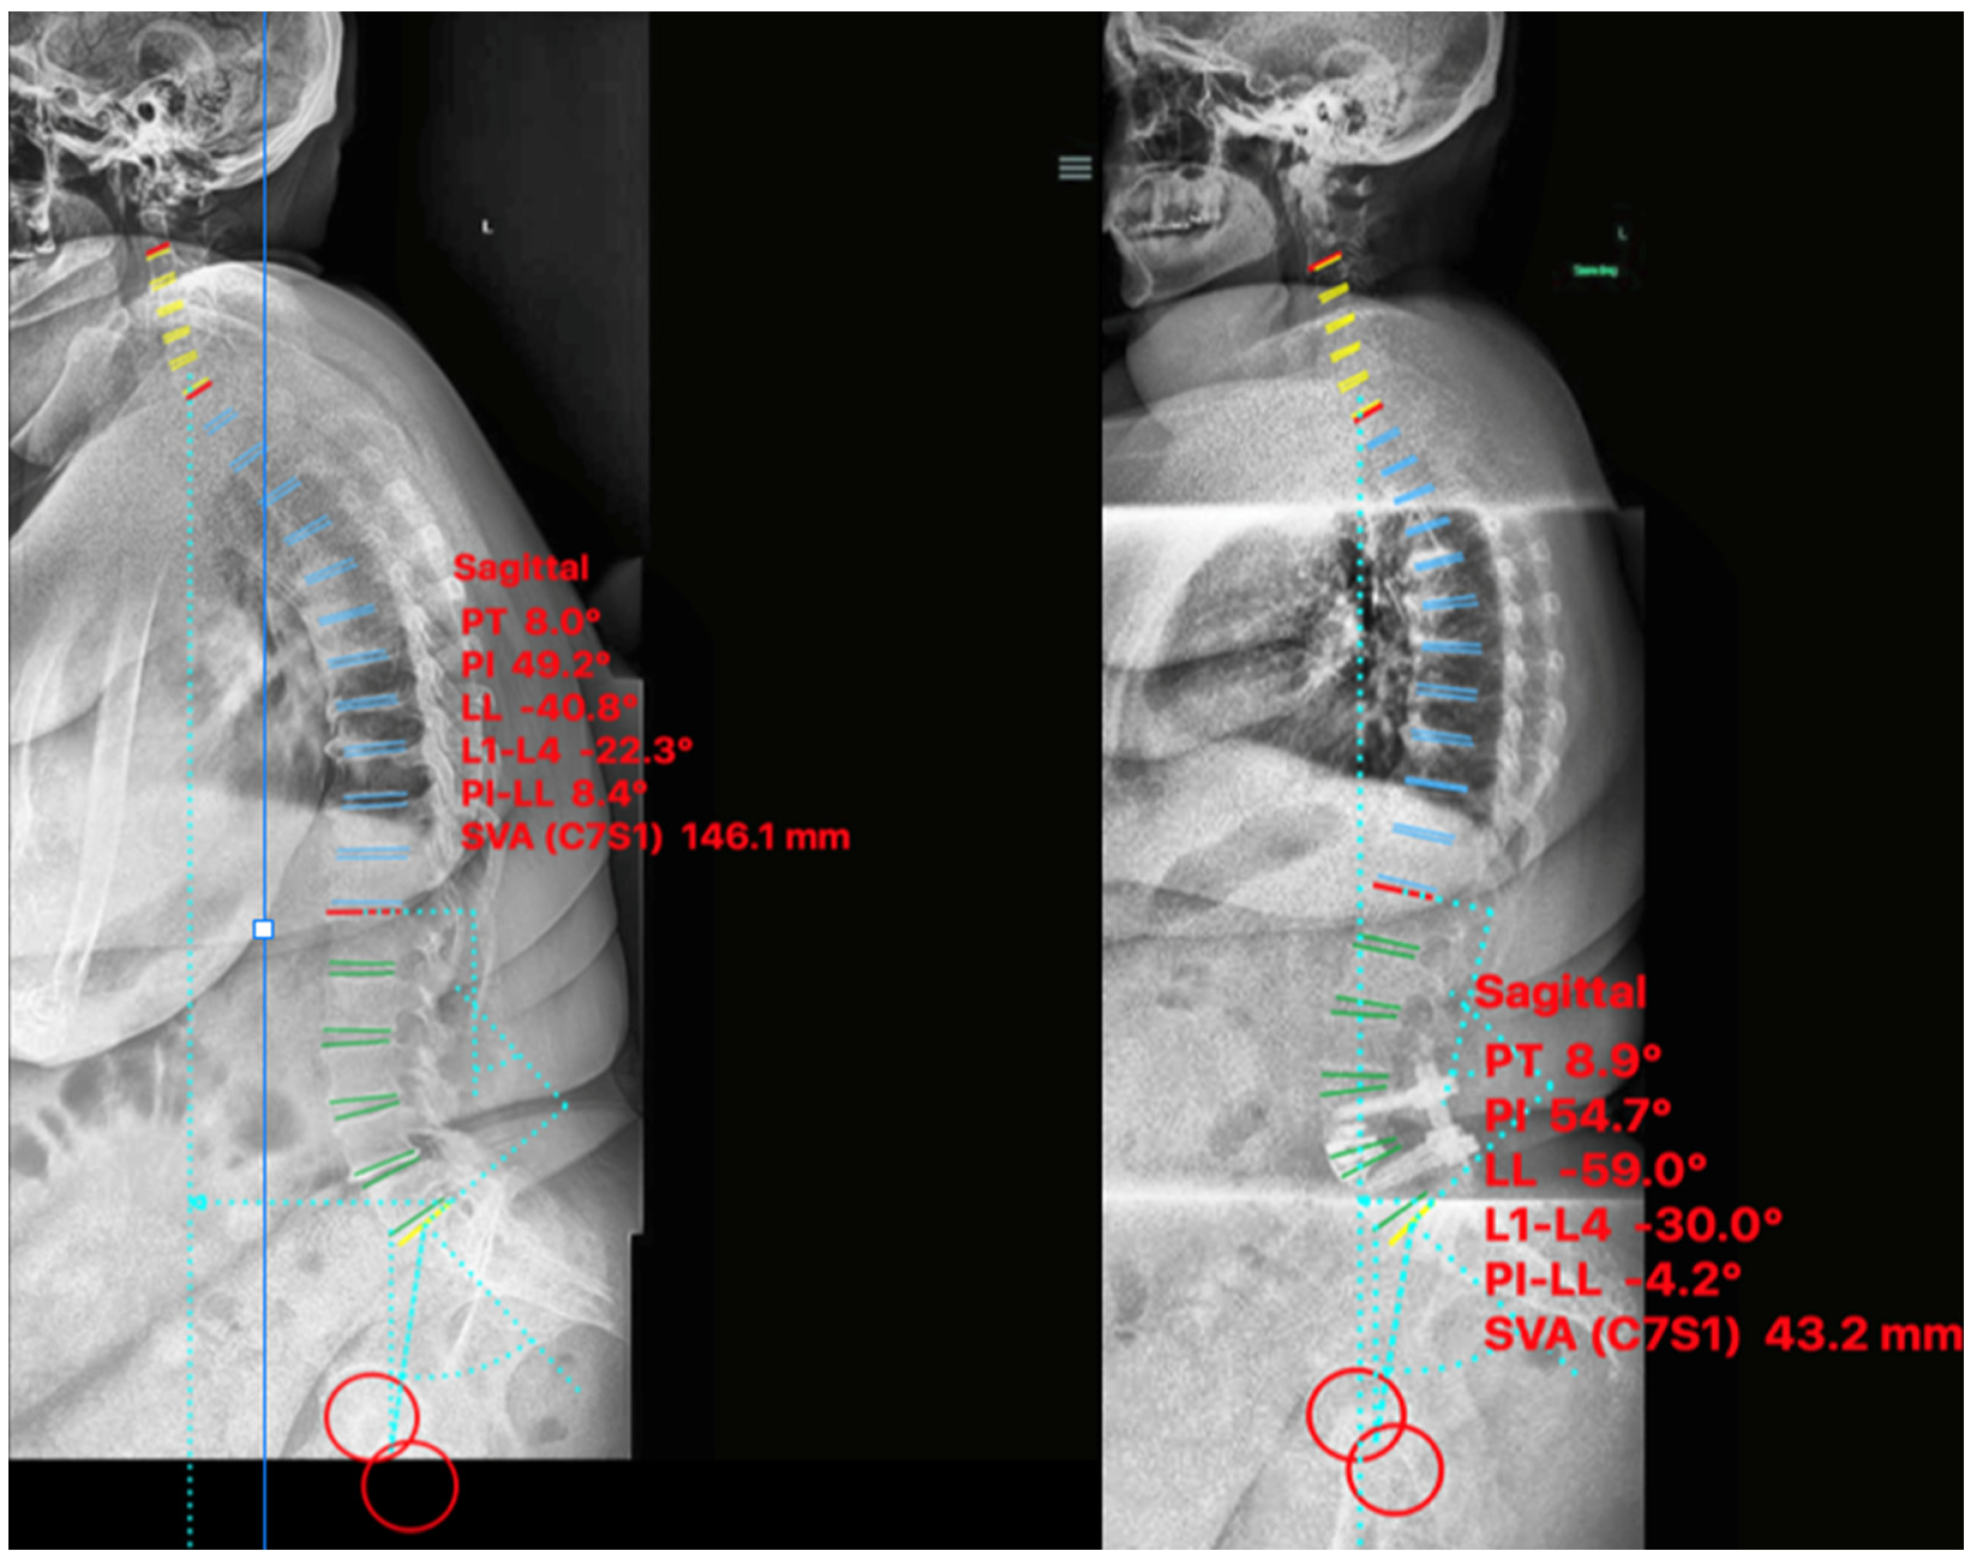

2.4.3. Case III

2.5. Non-ACR Cases

2.5.1. Case IV